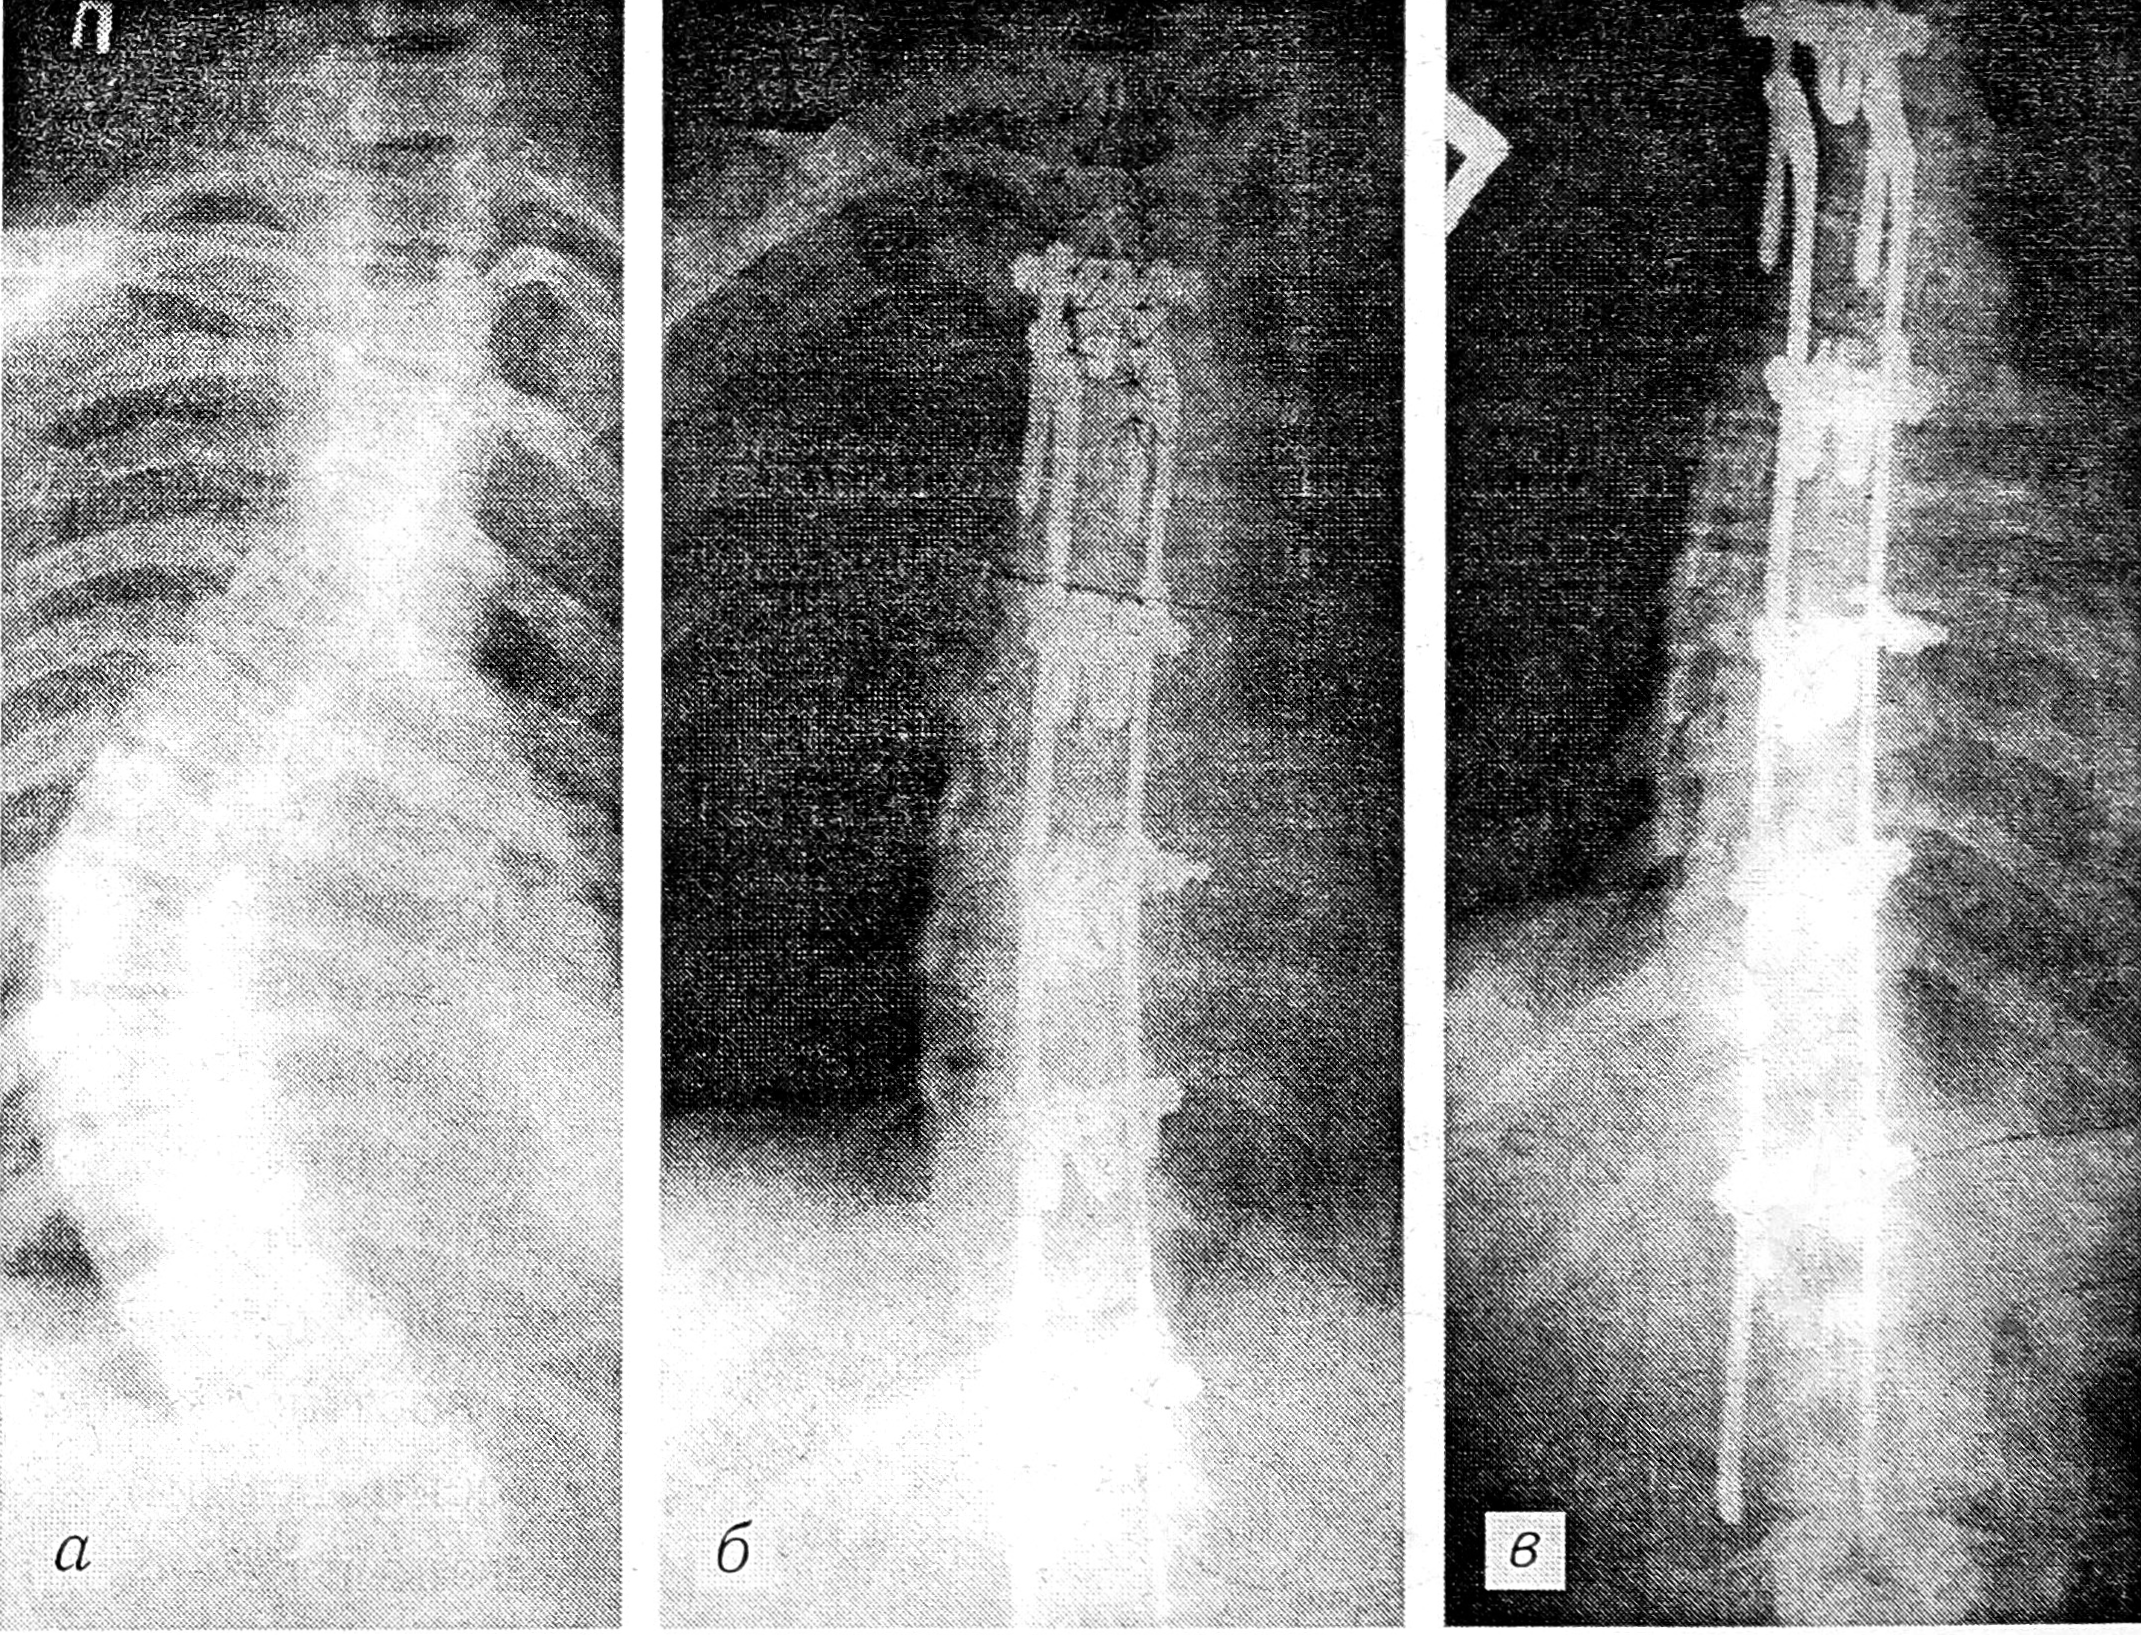

Рис. 2. Спондилограммы больной Е. 15 лет.

a — до операции: фронтальный угол 56°, торсия 30°; б — после операции: фронтальный угол 20°, торсия 15°, коррекция 65%; в — через 1 год после операции: коррекция сохраняется.

Послеоперационная коррекция была в диапазоне 50—100%, в среднем 74%, однако в группе больных сколиозом III степени средняя послеоперационная коррекция была выше — 86%. В сроки до 3 лет после операции отмечается стабильная фиксация конструкцией позвоночника, коррекция не утрачена (рис. 1, 2).